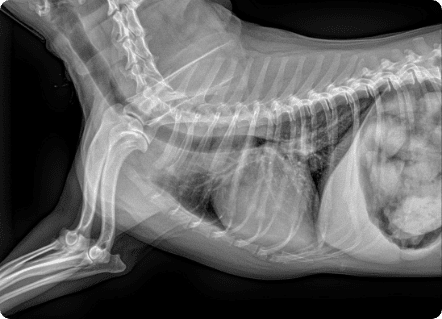

일산시티동물의료센터 방사선(X-ray) 검사는 탁월한 영상품질로 세밀하고 선명한 영상을 얻을 수 있습니다.